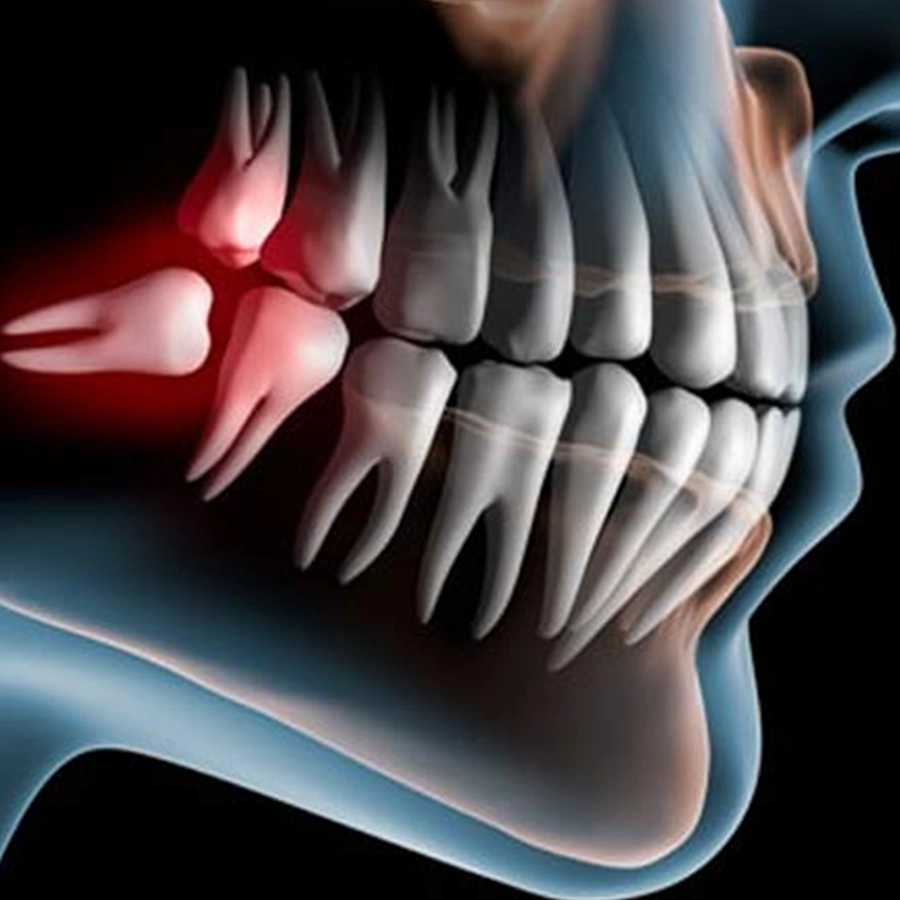

The Surgical Extraction Course is aimed at general dentist who are seriously interested in up-skilling, learning, and building confidence in their surgical extraction technique.

- Extraction of difficult 3rd molar teeth

- Combination of impacted cases, fractured teeth and wisdom teeth

The course is a five‑day intensive programme in Chennai including supervised surgical removal of at least ten teeth per participant, covering impacted wisdom teeth fractured and third molars, guided by specialist mentors at a recognised dental university setting.